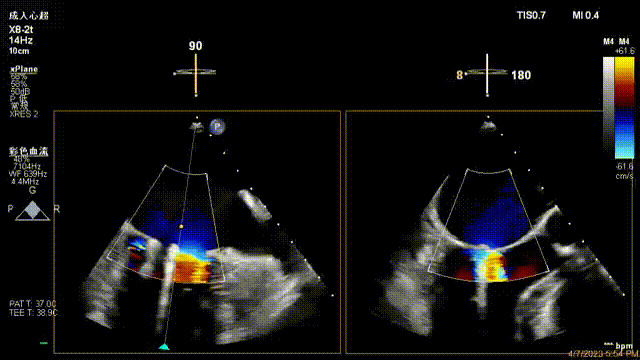

術(shù)后超聲顯示二尖瓣反流消失,瓣膜夾穩(wěn)定

接受治療的是一例器質(zhì)性重度二尖瓣反流(DMR)患者,主訴“反復(fù)活動后胸悶,氣促3年余”。術(shù)前超聲顯示,雙房增大,二尖瓣脫垂伴重度反流,輕度三尖瓣反流,輕度肺高壓,升主動脈增寬。手術(shù)經(jīng)股靜脈-房間隔入路,采用全身麻醉插管,在TEE和DSA引導(dǎo)下完成房間隔穿刺。置入JensClip瓣膜夾系統(tǒng)后,在左房調(diào)整瓣膜夾的位置和軸向,后進(jìn)入左室,在TEE引導(dǎo)下捕捉二尖瓣前后瓣葉,并關(guān)閉瓣膜夾。經(jīng)TEE反復(fù)確認(rèn)手術(shù)效果后最終鎖定并釋放瓣膜夾。術(shù)后即刻超聲顯示瓣膜夾位置穩(wěn)定,功能良好,術(shù)前二尖瓣反流4+,術(shù)后0反流,肺靜脈逆流和左房壓都顯著好轉(zhuǎn),手術(shù)圓滿成功(以上數(shù)據(jù)都來源于醫(yī)院的臨床記錄)。術(shù)后患者狀態(tài)良好,目前已安排出院。